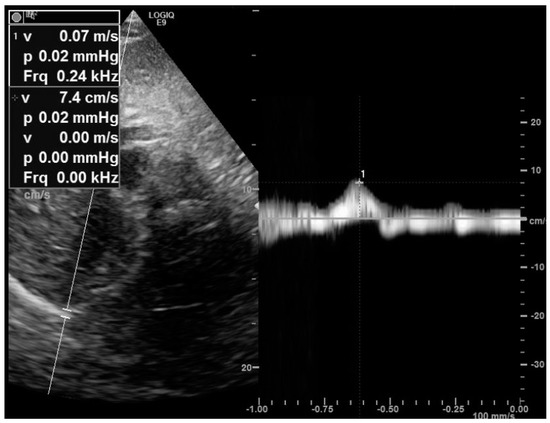

4.1. The Subcostal Approach